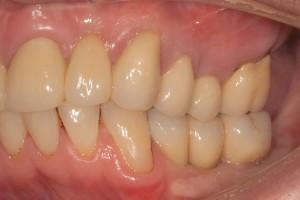

Before implants placement and correction of gum line and ready for implants.